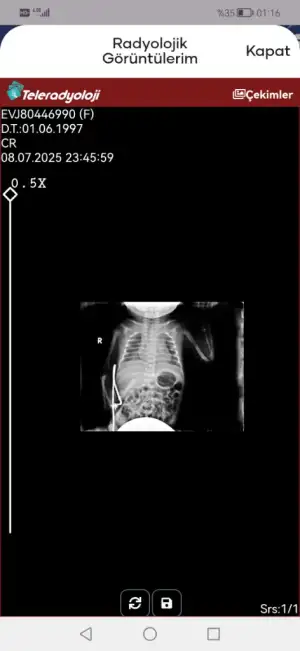

Yenidoğan pnömöni

Veriyorlar yeni yeni. 2 gündür entübe değil ama bugün nasıl şuan bilemiyorum kan değerleri bu şekilde

Evet entübasyon hortumu görünmüyor iki hortum olmalıydı ağzında. Entübeden ayrılması da iyi bir şey süt de azıcık gaz yapmış hatta bebişe. Süt aldıkça bu değerler toparlanır. Kan gazına göre bebeğiniz solunumu tölere edebiliyor diyebiliriz bunlar güzel haberler